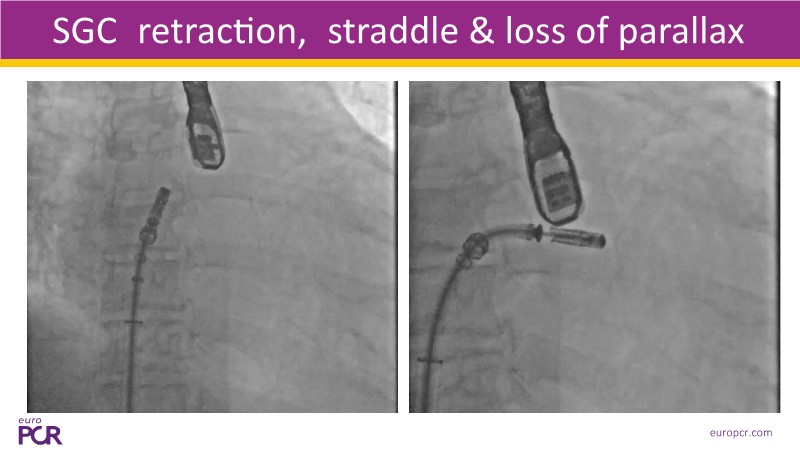

- To discover tips and techniques for mitral TEER in patients with challenging anatomy and difficult imaging